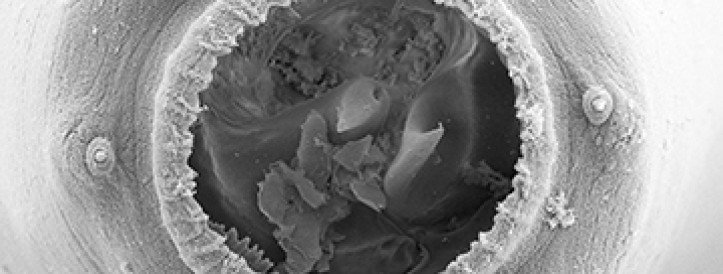

Last year, Scientific Reports retracted a paper comparing the condition, which the authors dubbed Middle East Pain Syndrome, to rheumatoid arthritis for failing to establish a clear distinction between the two ailments. The new article, published in January 2025 in BMC Rheumatology with two overlapping authors, compares MEPS to fibromyalgia, claiming it is distinct for its "hand tufts spur-like excrescences".